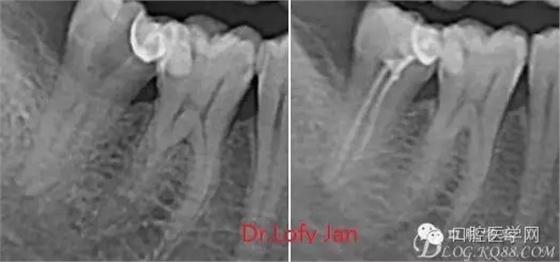

曲面斷層片在未試尖根管治療中的病例整理

前言:自己做的一些曲面斷層片在未試尖根管治療中的病例整理,發(fā)現(xiàn)問題很多包括自身的,技術(shù)的,還有設(shè)備的問題,予以總結(jié)整理并期待進(jìn)一步提高。

《數(shù)字化根尖片、曲面斷層片、CBCT測(cè)量牙齒長(zhǎng)度準(zhǔn)確性的比較研究》文中顯示:平行投照數(shù)字化根尖片影像長(zhǎng)度和牙齒實(shí)際長(zhǎng)度之間無顯著性差異(P0.05);數(shù)字化曲面斷層片影像長(zhǎng)度和牙齒實(shí)際長(zhǎng)度之間有顯著性差異(P0.05),平均失真率為17.05%。CBCT冠狀面測(cè)量結(jié)果中除上頜前磨牙區(qū)、下頜前磨牙區(qū)與真實(shí)長(zhǎng)度差異無統(tǒng)計(jì)學(xué)意義(P0.05)外,其余6個(gè)分區(qū)差異均有統(tǒng)計(jì)學(xué)意義(P0.05);矢狀面測(cè)量結(jié)果中上頜磨牙區(qū)、下頜磨牙區(qū)、下頜前磨牙區(qū)、下頜尖牙區(qū)、下頜前牙區(qū)與真實(shí)長(zhǎng)度比較差異均有統(tǒng)計(jì)學(xué)意義(P0.05)。結(jié)論平行投照數(shù)字化根尖片較曲面斷層片和CBCT能更加精確地反映牙齒的真實(shí)長(zhǎng)度。

病例分析:曲面斷層片在x線輔助診斷與檢查中目前大多數(shù)文獻(xiàn)和著作都建議只能作為初診拍片檢查手段,不能作為終末疾病的確診與手術(shù)療效的評(píng)價(jià)指標(biāo),臨床大部分中小型門診都因?yàn)樵O(shè)備不齊全導(dǎo)致信息偏差很大。